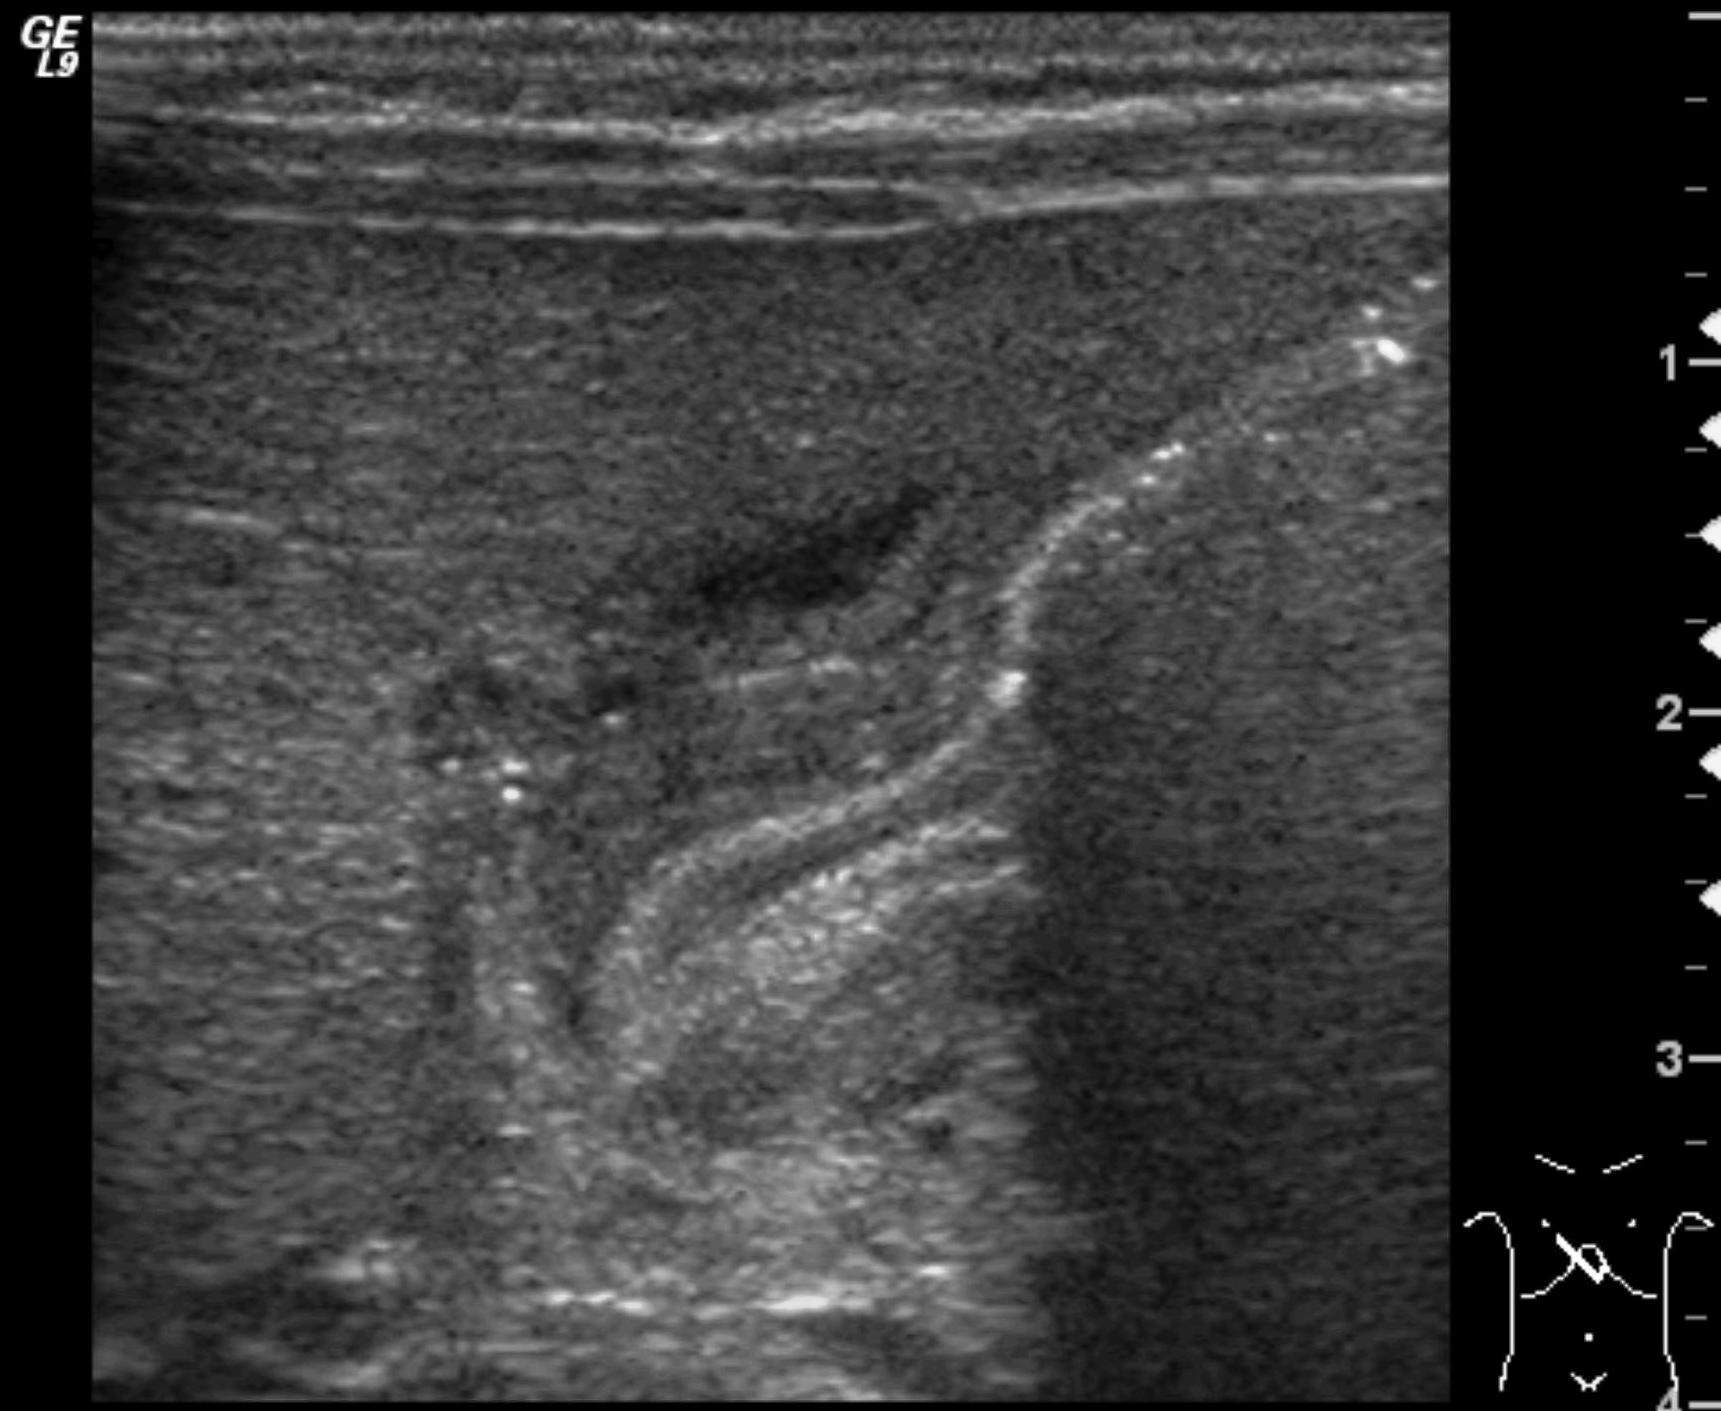

Image

38. US, longitudinal. On the proximal part of the right femur, the periosteal soft tissue is hypoechoic, the flow is increased. Osteomyelitis